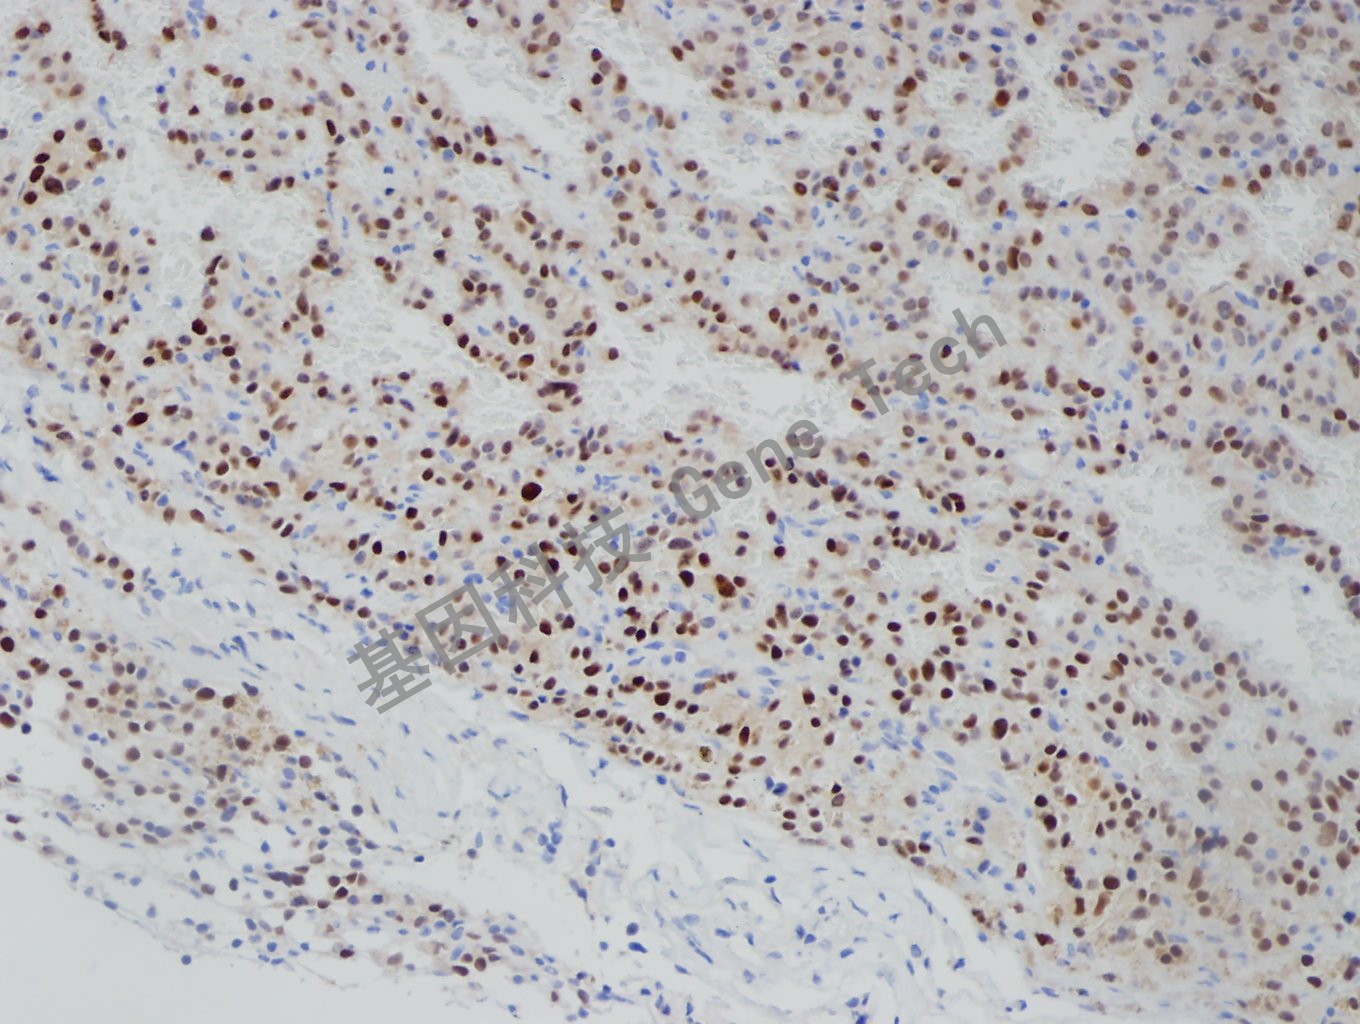

垂体瘤石蜡切片,用 T-Pit(GT2318)染色,细胞核阳性,DAB显色。